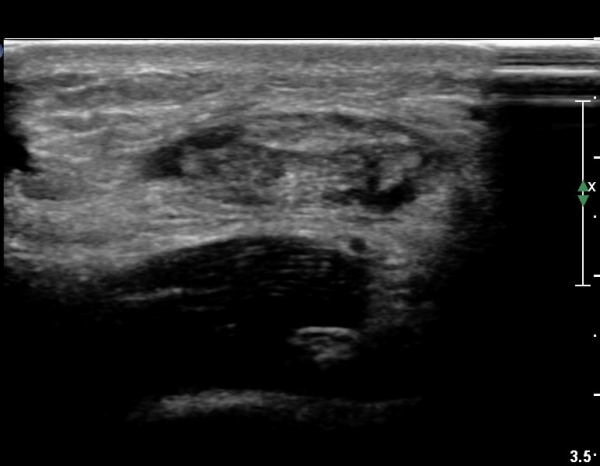

¾ÆÅ³·¹½º°Ç Á¾´Ü¸é°Ë»ç¿¡¼ ¾ÆÅ³·¹½º°Ç Àú¿¡ÄÚ ºÎÁ¾, ¿¬°á¼º ¼Ò½Ç, °ÇÁÖÀ§ ¼ö¾×Àú·ù ¼Ò°ßÀ» º¸ÀÓ(»çÁø 2, 3, 4, 5).

¾ÆÅ³·¹½º°Ç Ⱦ´Ü¸é°Ë»ç¿¡¼ ¾ÆÅ³·¹½º°Ç Àú¿¡ÄÚ ºÎÁ¾, ¿¬°á¼º ¼Ò½Ç, °ÇÁÖÀ§ ¼ö¾×Àú·ù ¼Ò°ßÀ» º¸ÀÓ(»çÁø 6, 7, 8).